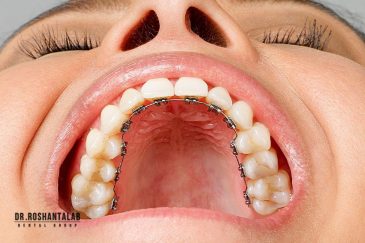

برای اصلاح طرح لبخند بدون جلب توجه، از جدیدترین تکنولوژی الاینر و ارتودنسی شفاف استفاده کنید. ما تخصصیترین خدمات ارتودنسی دندان را با قیمت مناسب و شرایط اقساط ویژه ارائه میدهیم.کاشت دندان توسط بهترین متخصص ایمپلنت